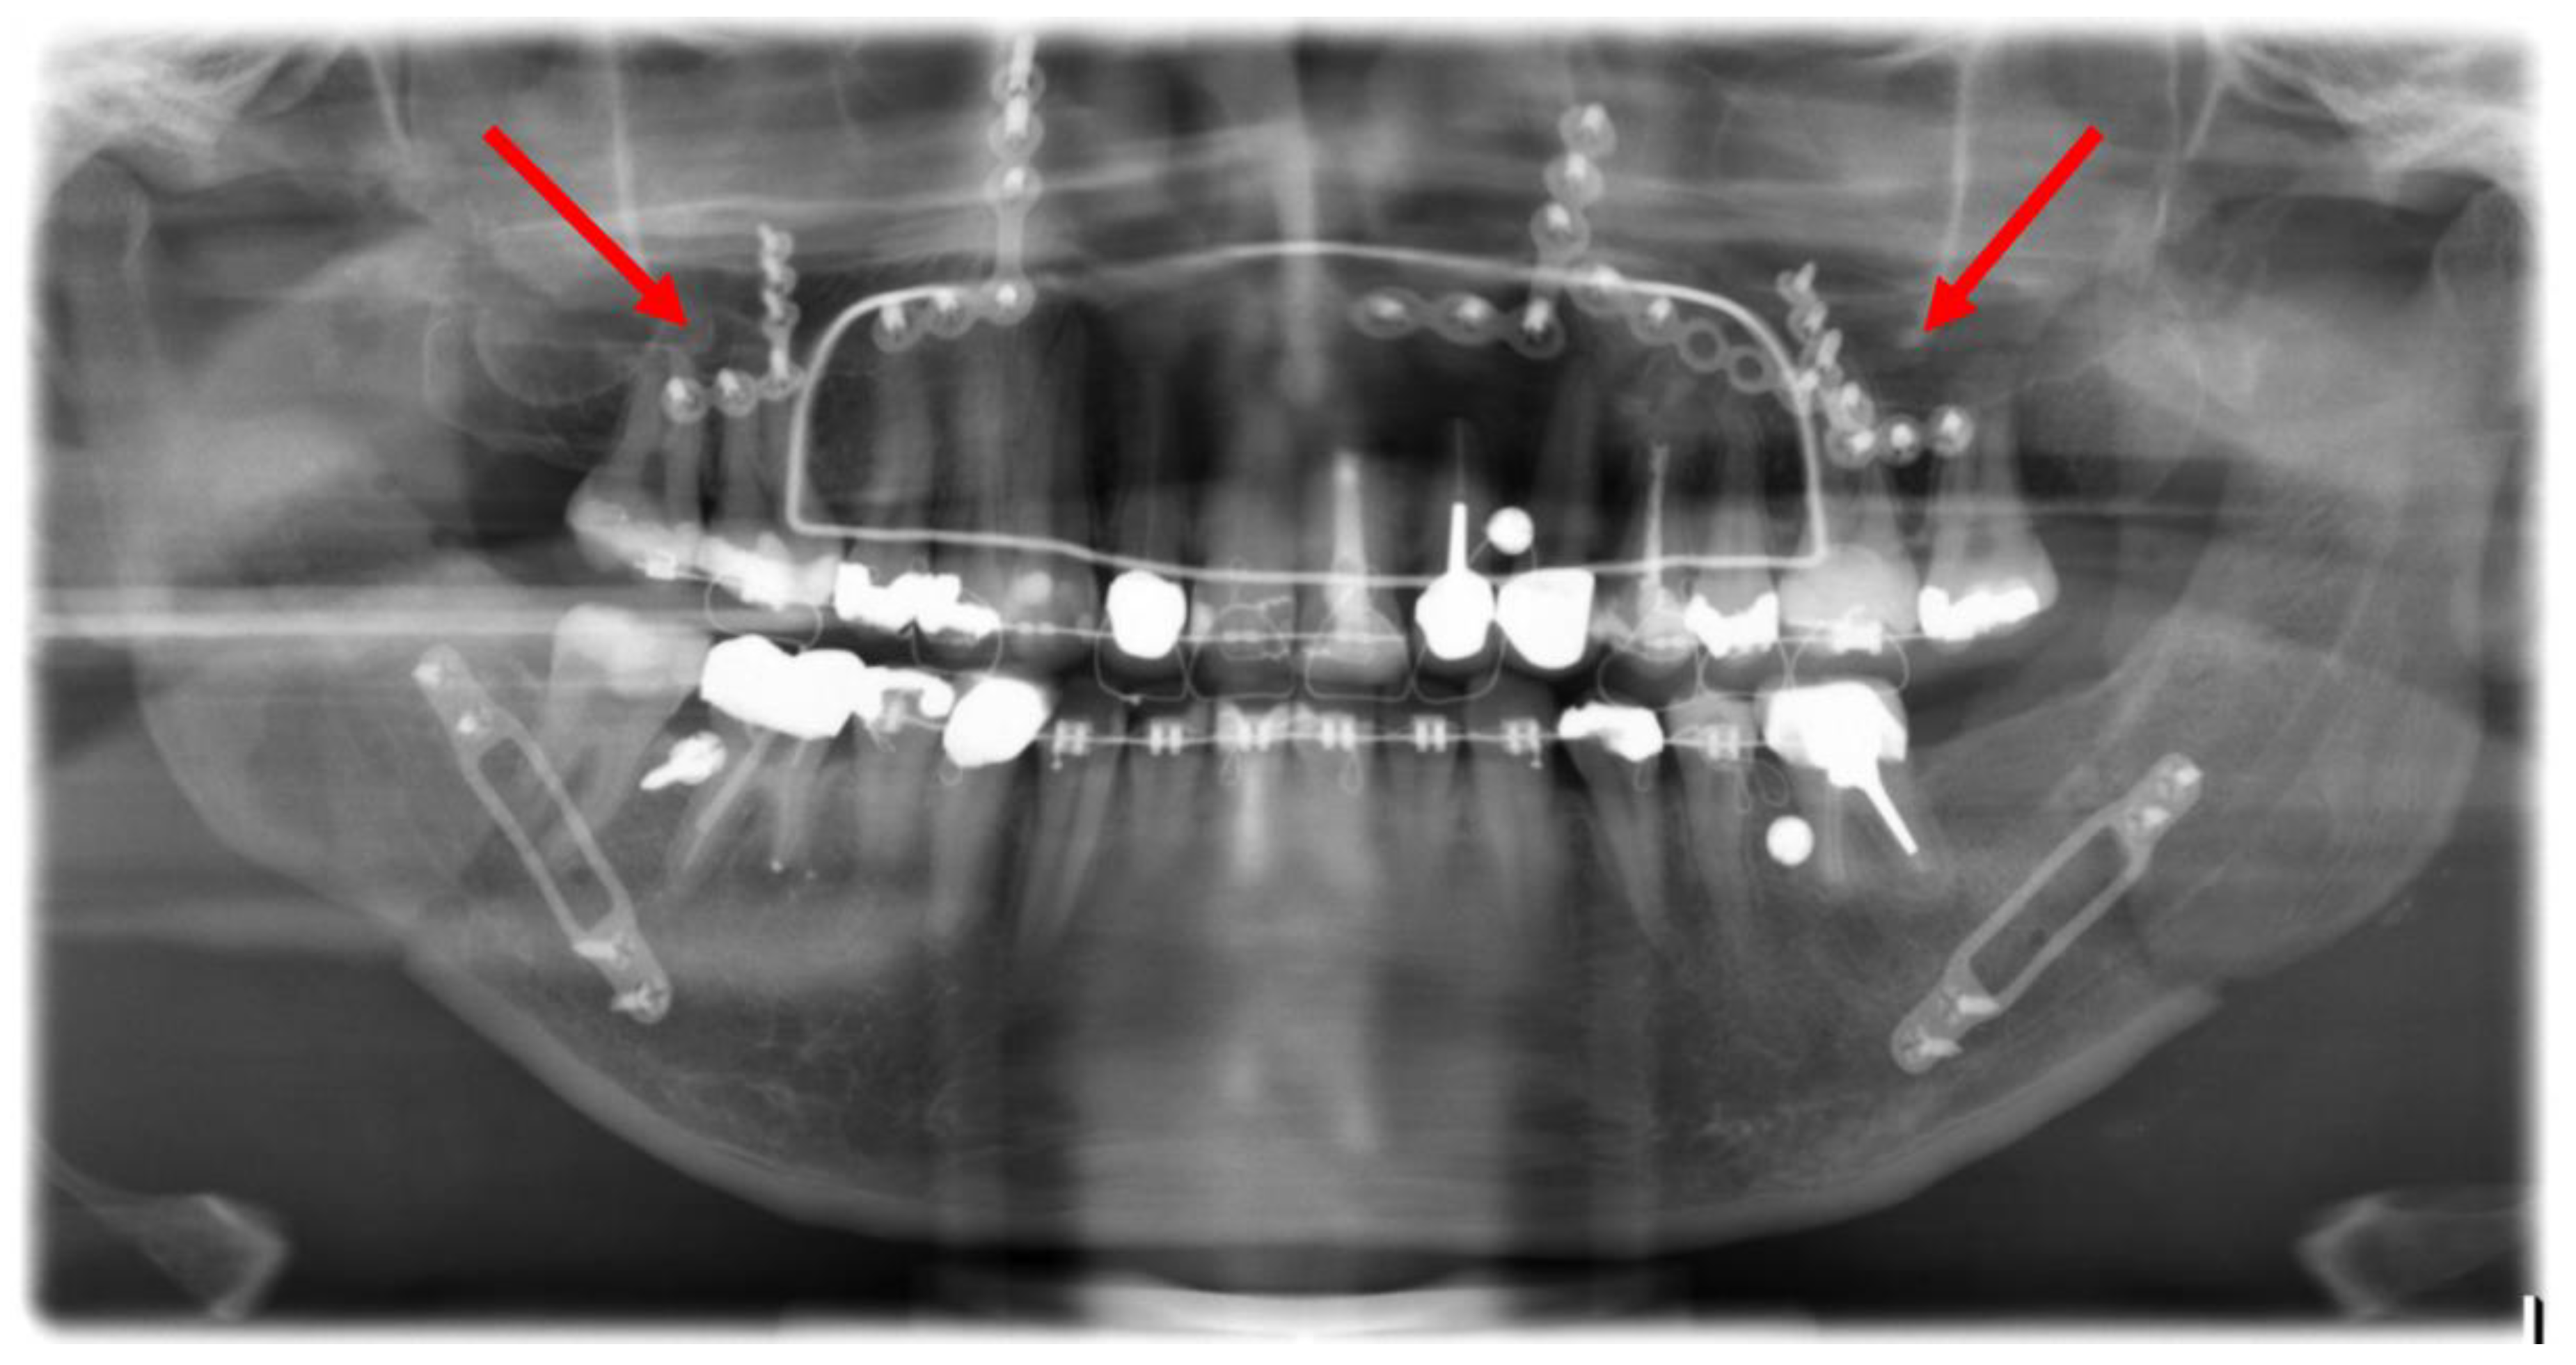

Figure 6.

Post-operative orthopantomogram after the conventional maxillary positioning, showing the projections of three osteosynthesis screws with the dental roots of the teeth 16 and 17 and the projections of four osteosynthesis screws with the dental roots of the teeth 26 and 27 (red arrows).

Figure 7.

Axial plane of post-operative CT scan. Image (1) shows an injury of the mesiobuccal tooth root of tooth 27, while in image (2), no root injury in the right maxillary molars is detected (red arrows).

In the Maxilla Conventional cohort, 94 radiological projections of osteosynthesis screws with the dental roots were detected in the post-operative OPG. In contrast, post-operative CT imaging detected only 10 dental root injuries. In the Maxilla PSI cohort, 64 radiological projections were detected; however, no dental root injury could be detected in post-operative CT imaging. In the mandible, a total of 106 projections in the premolar and molar region were recorded in the post-operative OPG, but only 12 root lesions were detected in post-operative CT scan.